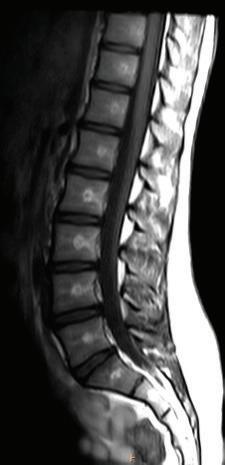

Sagittal CT images are shown as though the patient is looking toward the viewer’s left (Fig. 1-19).